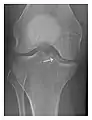

Occult osseous injuries may result from a direct blow to the bone by compressive forces of adjacent bones against one another or by traction forces during an avulsion injury. Lesions in the tibial plateau, hip, ankle, and wrist are often missed. In a tibial plateau fracture, any disruption of the posterior and anterior cortical rims of the plateau should be sought. Impaction of subchondral bone will appear as an increased sclerosis of the subchondral bone (Figure 1). In the hip, posterior acetabular fractures also present subtle radiographic findings. The acetabular lines should then be carefully examined keeping in mind that the posterior rim, which is harder to see on X-rays, is more frequently fractured than the anterior rim (Figure 2). In the wrist, detection of carpal bone fractures is often challenging, with up to 18% of scaphoid fractures radiographically occult. Carpal fractures, especially the scaphoid, are associated with the risk of avascular necrosis. In apparently normal wrist radiographs from symptomatic patients, if there is history of a fall on an outstretched hand with pain in the anatomic snuffbox, suggesting scaphoid injury, the initial examination with posteroanterior, lateral, and pronation oblique views must be complemented by other specific views such as supination oblique and the "scaphoid" view A careful examination of cortices for evidence of discontinuity or offset and cancellous bone for lucency is necessary (Figure 3).[1]

- a

- b

- c

Figure 3: A 26-year-old man presenting with wrist pain after being assaulted. (a) Initial anteroposterior radiograph shows a subtle linear lucency within the scaphoid extending to the scaphocapitate articular surface that was overlooked (arrow). (b) Initial "scaphoid" view was negative. (c) Followup anteroposterior radiographs, 12 days later, shows obvious scaphoid fracture (arrows).[1]